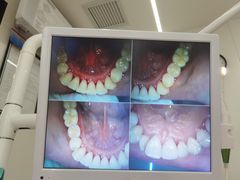

• 牙博士口腔品牌连锁(杨浦店)

• -牙博士口腔品牌连锁(杨浦店)

猫咪小乖123 | 21-08-16

可爱的世界 | 21-08-16